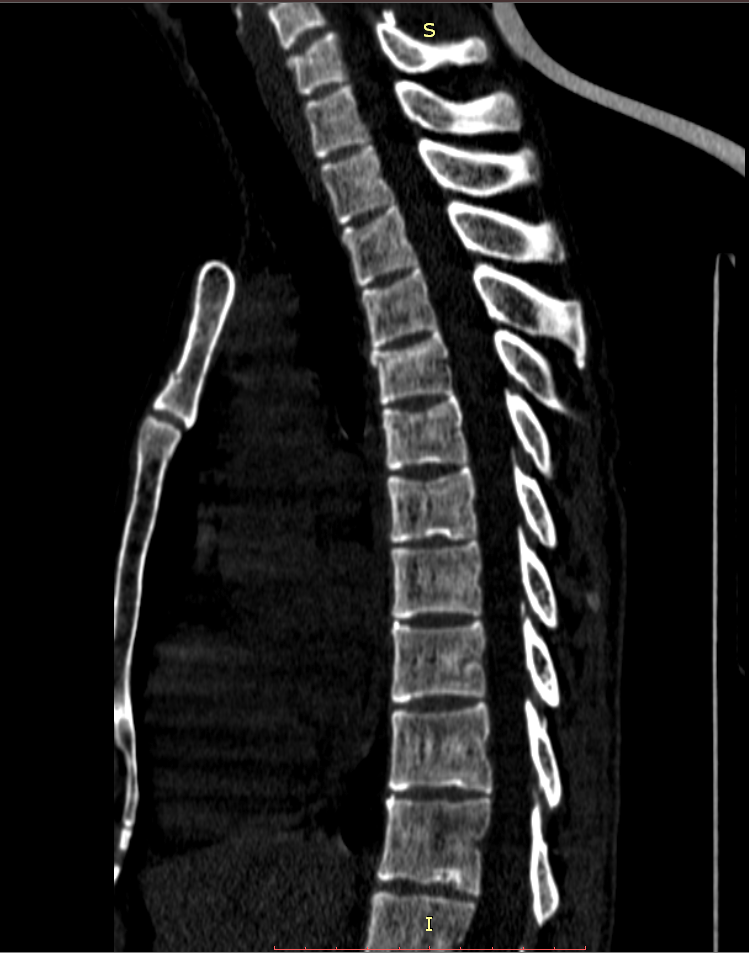

Здравствуйте! Меня сбил автомобиль. Бригада скорой помощи доставила меня в стационар с диагнозом - сотрясение мозга, ушиб грудного отдела позвоночника, компрессионный перелом грудного отдела позвоночника. При поступлении в стационар мне было сделано несколько рентгеновских снимков и поставлен диагноз - компрессионный перелом 4 грудного позвонка. Из-за "мутных" рентгеновских снимков через 9 дней мне сделали КТ и диагноз сняли на основании этого заключения.Судебная медицина - Прикрепленное изображение Мне сказали что перелом шейного позвонка у меня старый и поменяли диагноз - ушиб верхне-грудного отдела позвоночника, болевой синдром. По запросу я получила копию записи КТ. Всю запись КТ выложить не могу, т.к. не могу убрать фамилию. Выкладываю некоторые снимки: Судебная медицина - Прикрепленное изображение Судебная медицина - Прикрепленное изображение Судебная медицина - Прикрепленное изображение Судебная медицина - Прикрепленное изображение Судебная медицина - Прикрепленное изображение Судебная медицина - Прикрепленное изображение Судебная медицина - Прикрепленное изображение Действительно ли по этим снимкам можно сказать, что перелом шейного позвонка "старый"? Правильно ли описание КТ? Я не эксперт, но по-моему 5 грудной позвонок тоже поврежден. Можно ли оспорить заключение врача делавшего КТ? Если можно, то как это сделать? Ведь речь идет об установлении причинно-следственной связи между ДТП и травмой, а до ДТП у меня никаких травм позвоночника не было. Может рентгеновские снимки тоже о чем то скажут.Судебная медицина - Прикрепленное изображениеСудебная медицина - Прикрепленное изображениеСудебная медицина - Прикрепленное изображение

Для этого надо исследовать все сканы. Желательно - с 3D-реформацией изображения. С внимательным анализом костной структуры на уровне дефекта (есть ли признаки отека костной ткани в его зоне, наличие реакции мягких тканей, состояние краев фрагментов и т.д.). Получите все сканы КТ на диске или на флешке (они должны храниться в архиве КТ). И проконсультируйте их у высококвалифицированного специалиста по КТ и/или в любом крупном Бюро судебно-медицинской экспертизе, в штате которого есть эксперт-рентгенолог. Возможно, понадобится сделать контрольное КТ исследование с целью обнаружения динамики выявленных изменений (впрочем, вопрос об этом будет решен после ознакомления рентгенолога с КТ, т.к., возможно, доп.исследование не будет необходимо или же более целесообразным окажется иной вариант лучевой диагностики). По результатам консультации станет понятно, есть ли реальные основания для заявления мотивированного ходатайства о назначении дополнительной или повторной экспертизы (как это сделать - подскажет Ваш адвокат).